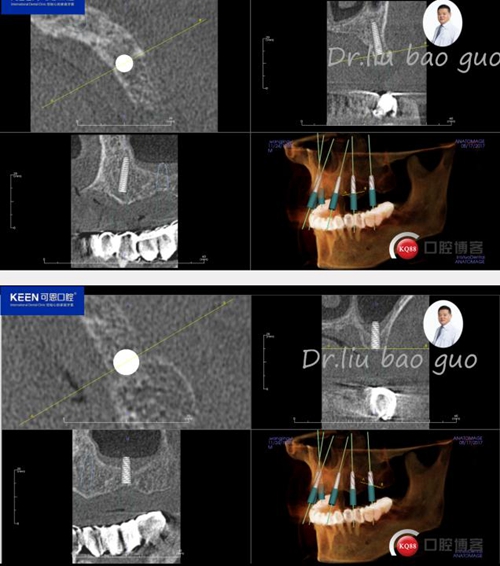

手術(shù)前種植軟件設(shè)計(jì)方案

數(shù)字化種植導(dǎo)板設(shè)計(jì)及制作